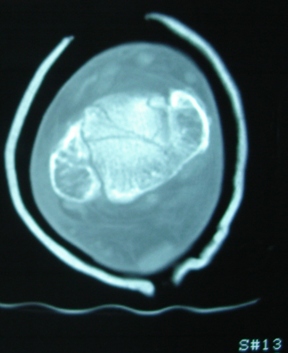

Продолжая тему представляю данные КТ нашей пациентки.

Вложение не в текстовом формате было извлечено…

Имя     : Скан 12.JPG

Тип     : image/jpeg

Размер  : 42408 байтов

Url     : http://weborto.net:8080/pipermail/ortho/attachments/20091107/a87a6ebe/attachment-0006.jpeg